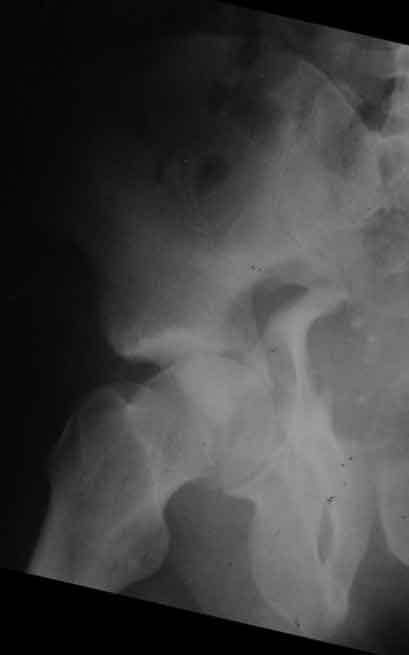

Дополнение, минимальный набор необходимых прекций, необходимых для лечения повреждений вертлужной впадины

Фас. Inlet

Подвздошная Запирательная